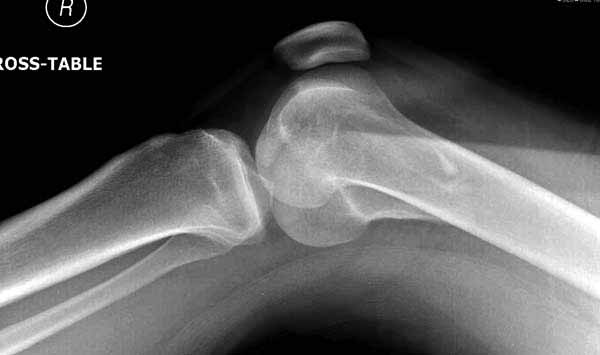

Ответ на эту часть Вашего поста – вложенный файл. Больная оперирована неделю назад по поводу открытого перелома дистального эпиметафиза бедренной кости. После операции она идёт в рентгенкабинет для выполнения послеоперационной контрольной рентгенографии, представленной на слайдах 10 и 11. Узнав, почему её фотографируют, просила передать Вам, Антон, привет.

В приложении пример недавней операции, C3, открытая репозиция, фиксация мыщелков спицами и винтами, ретроградный синтез большеберцовым гвоздем 10,5 мм диаметром, винты 5 мм.

Позволю себе напомнить коллегам ещё раз, что являюсь сторонником антеградного остеосинтеза при переломах дистального эпиметафиза бедренной кости. Такая приверженность основана не на преимуществах внесуставного введения стержня или большем проценте положительных результатов. Она основана на возможности обеспечить блокирование на минимальном расстоянии от суставной поверхности в нескомпрометированной кости и, таким образом стабилизировать максимально низкие переломы. В приведенном Вами случае самый дистальный из блокирующих винтов проведен на расстоянии более 2 см от конца стержня. Из-за того, что к стержню присоединяется кондуктор, на стержне теряется 1-1,5 см его длины, где можно было разместить отверстия для блокирования. И что более важно, вместе с потерянной для этой цели длиной стержня утрачивается для размещения блокировочных винтов, пожалуй, самая ценная часть дистального эпиметафиза бедренной кости. Проблемы дистального блокирования в разных плоскостях, локализации точки ввода стержня при антеградном остеосинтезе – это всё решаемые технические проблемы. Но антеградный остеосинтез низких дистальных переломов бедра при адекватном блокировании в нескомпрометированной кости обеспечивает решение стратегической задачи – стабильный остеосинтез и возможность нагрузки.